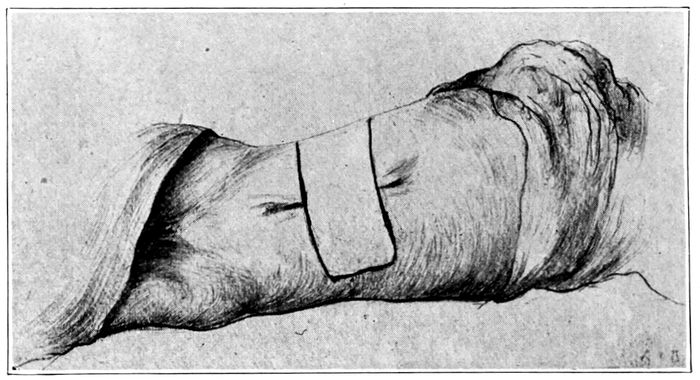

Examples of imperfect nipples |

245 |